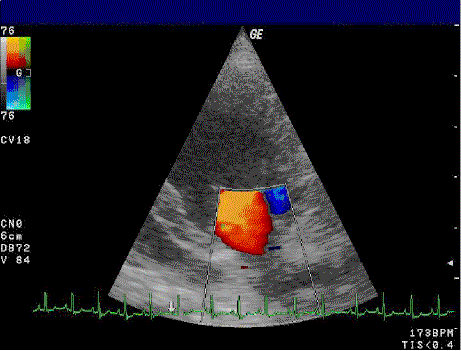

De gouden standaard voor de diagnose en de ernst van de mitralisinsufficiëntie is het afnemen van een echocardiogram. Verder kan een thoraxfoto bijdragend zijn. De aan- of afwezigheid van longoedeem kan middels een thoraxfoto worden beoordeeld en een vergroot linkeratrium kan leiden tot een zichtbaar stompe carinahoek van meer dan 60 graden.